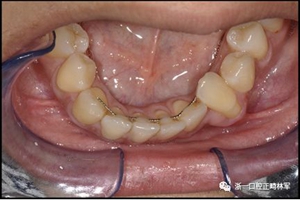

圖17.治療進(jìn)展:A和B,二次手術(shù)后愈合; C和D,幾個(gè)月后牙根扭矩的改善。

圖18.脫粘后的最終圖像:A,正面視圖; B,咬合面視圖。 進(jìn)一步的牙齒移動以糾正輕度前牙開合被認(rèn)為不符合患者的最佳利益。